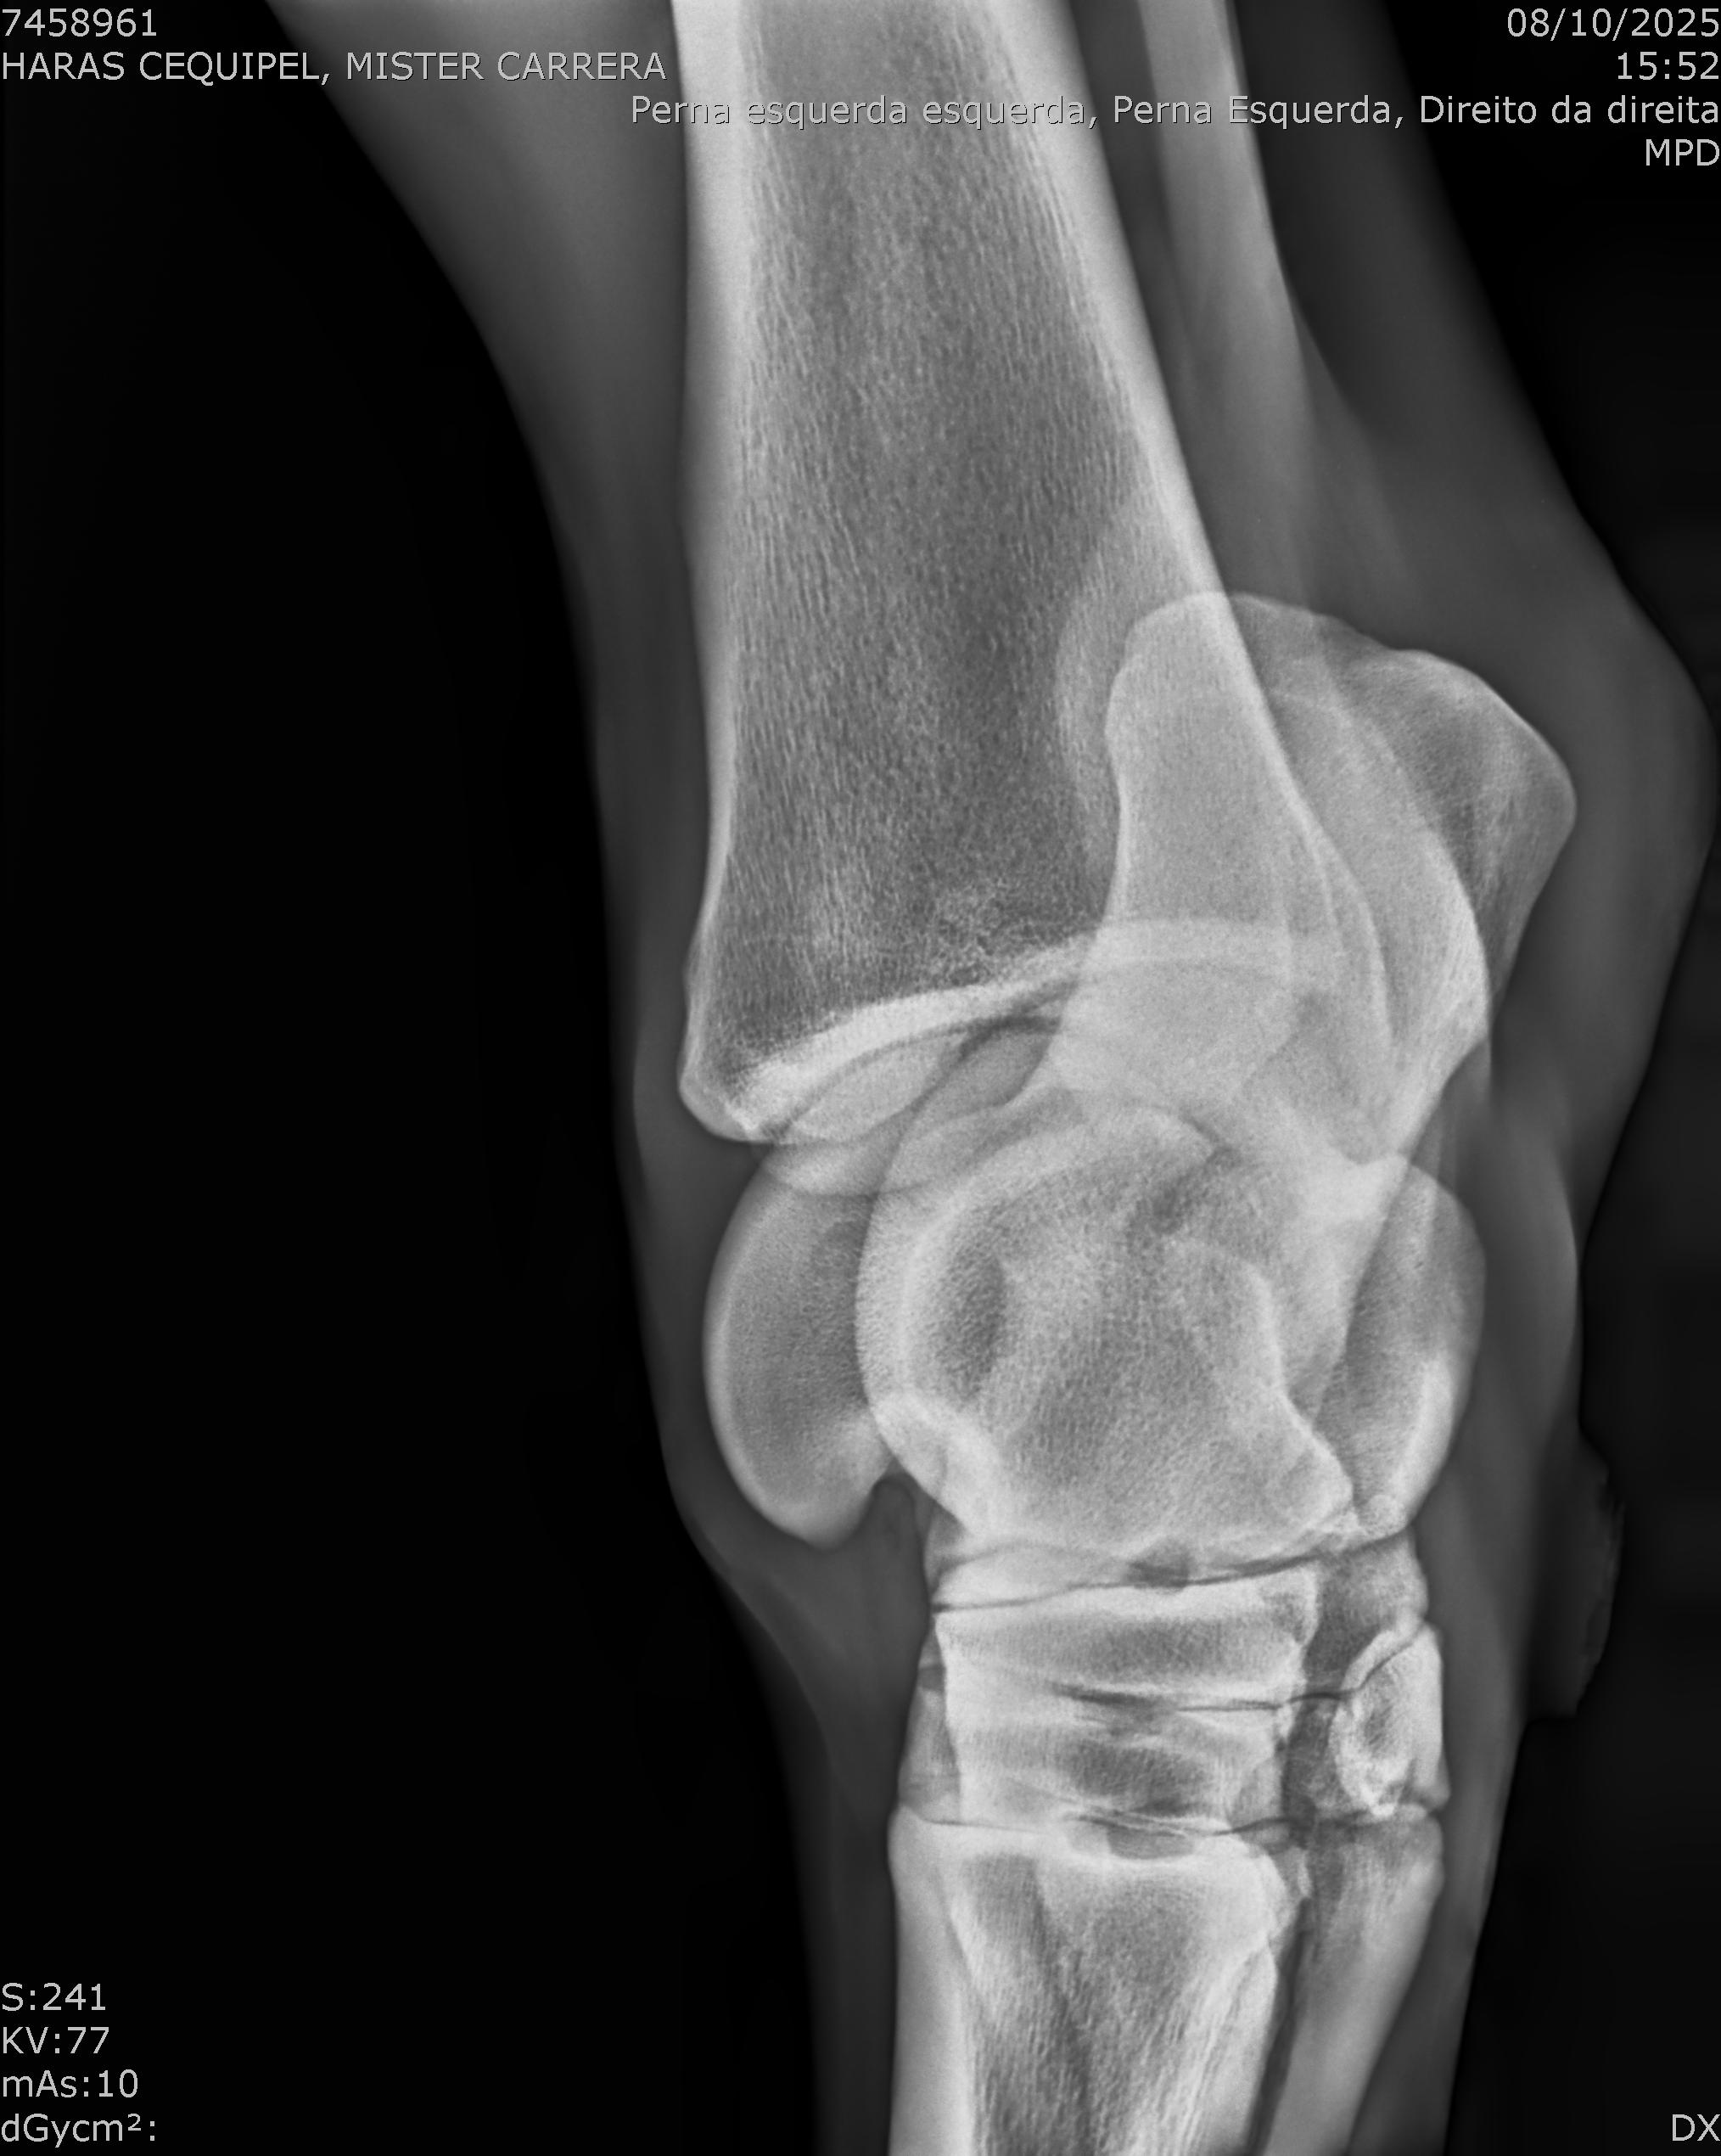

:: RAIOS-X DO LOTE